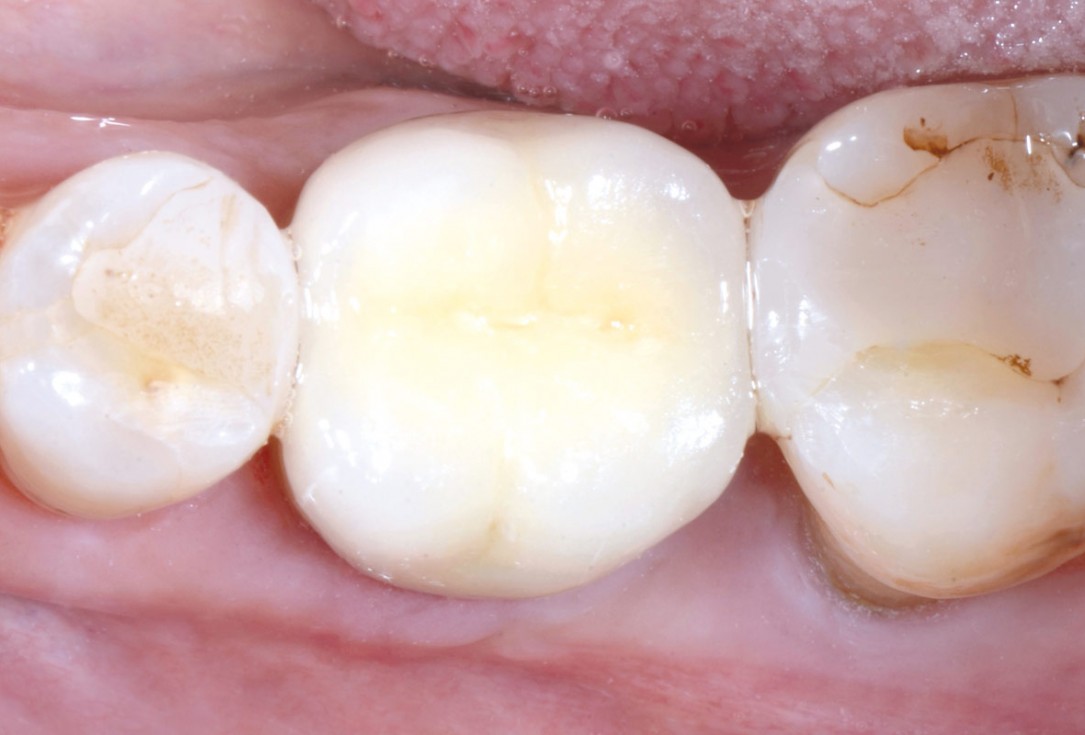

Immediate implant placement using cerabone® and collagen fleece - Dr. D. Jelušić

Pre-operative situation showing tooth 21 with deep periodontal pocket. Tooth presented with mobility grade III.